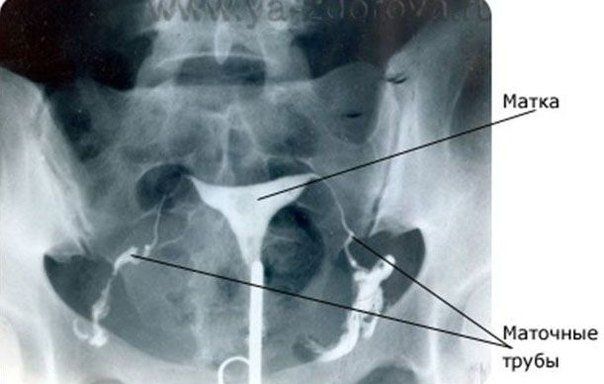

Гистеросальпингография (ГСГ) — это рентгенологический метод исследования полости матки и характера проходимости маточных труб с использованием контрастного вещества (водорастворимый йодсодержащий препарат). Данное исследование используется для уточнения или постановки диагноза. Гистеросальпингография выполняется в рентгенологическом кабинете совместно двумя врачами — гинекологом и рентгенологом.

Пациентка укладывается на стол в рентгеновском кабинете на спину с согнутыми в коленях ногами. Врач-гинеколог производит обработку антисептиком влагалища и шейки матки. Шейка матки фиксируется пулевыми щипцами, через цервикальный канал под контролем монитора вводится контрастное вещество в полость матки и, если трубы проходимы, в трубы и брюшную полость. Выполняется серия снимков на рентгеновском аппарате, которые затем оценивает и описывает специалист. Заключение о результатах ГСГ вместе со снимками выдается на руки пациентке.